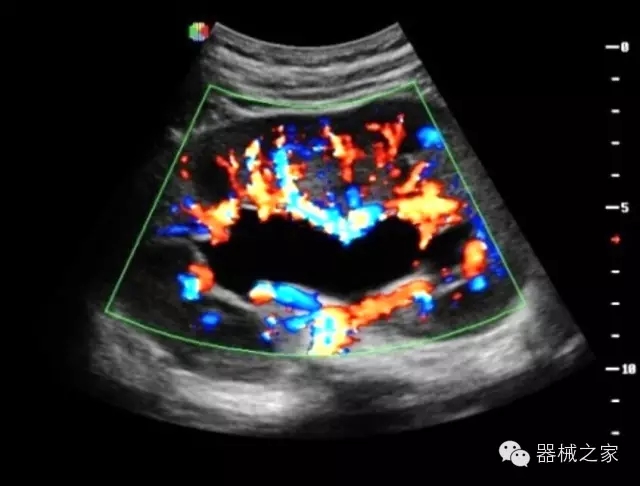

臨床圖片賞析

·飛依諾特有心臟純凈波探頭提供更好的穿透力和彩色敏感度,以及結(jié)合TView梯形拓展改善困難病人深部組織成像;

·獨(dú)有RF敏感血流使得心臟血流完美呈現(xiàn);